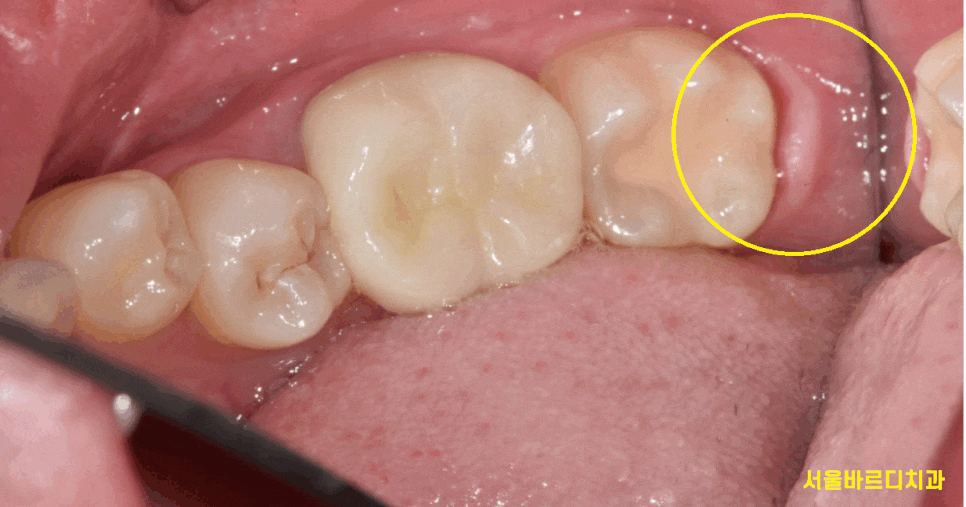

240729

예쁘게 올라오고

아래 치아와 맞닿아서 잘 쓰고 있었지만...

230725

맨 끝~~에 있어서 관리가 잘 안됐다.

충치가 생겼다.

그러면 뽑아야합니다.